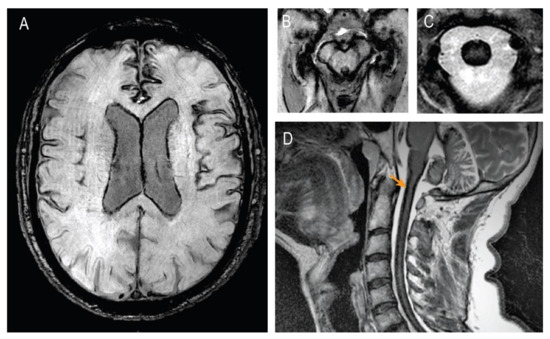

2. Case Presentation